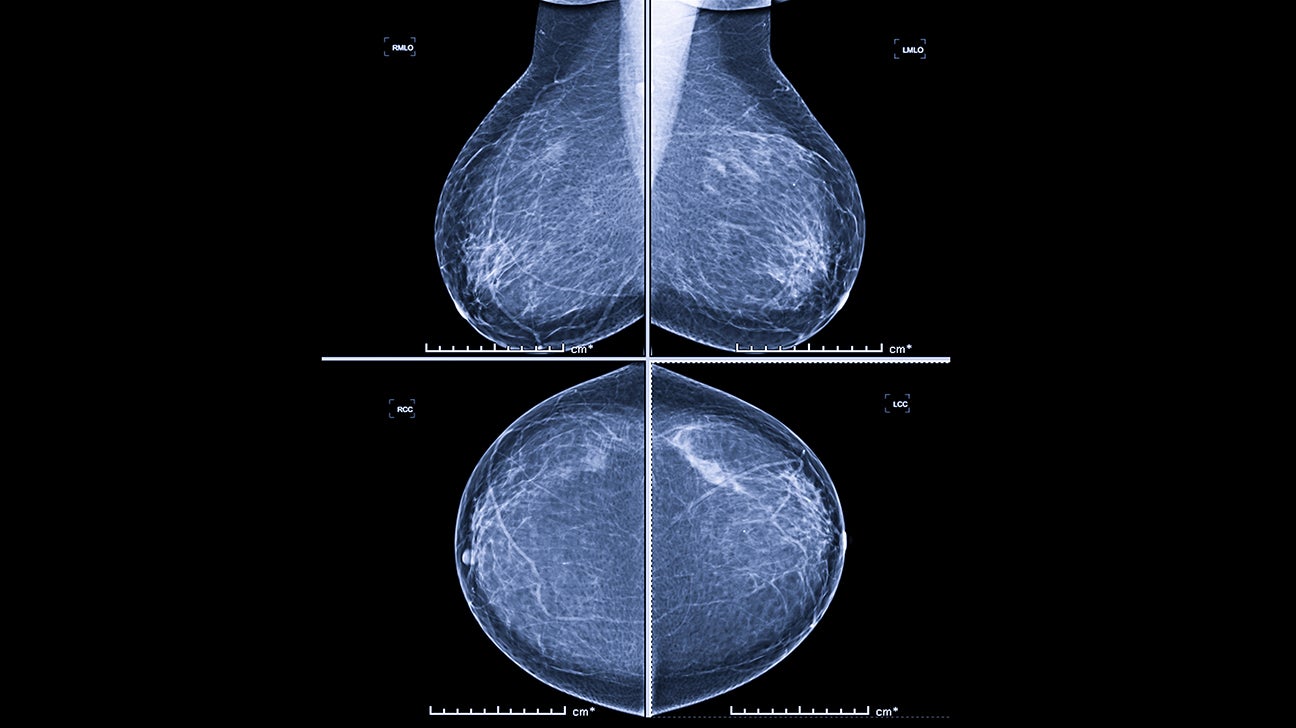

There’s a change from the last mammogram.

They appear as white spots or flecks on a mammogram but can't be felt during a breast exam. A new group has formed. For women treated for breast cancer in the past, calcifications may also be due.